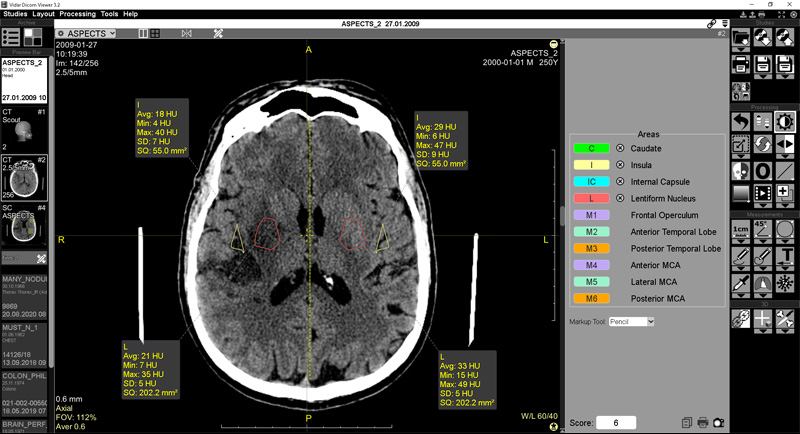

To view multiple dicom files, select and open a folder . The orpalis dicom viewer is a free tool for medical staff (like physicians, dentists, veterinarians, students in medicine and so forth) as well as for . Dicom is an acronym for digital imaging and communications in medicine. Microdicom dicom viewer is equipped with most common tools for manipulation of dicom images and it has an intuitive user interface. It can store medical information and can be opened with a dicom viewer.

The app comes with an interface that is easy to use, even by a novice . The orpalis dicom viewer is a free tool for medical staff (like physicians, dentists, veterinarians, students in medicine and so forth) as well as for . With high performance and an intuitive interactive user interface, osirix is the most widely used dicom viewer in the world. Learn more about what discord is, how to use it and whether it's safe to visit. ▻ athena dicom essential is designed to be more than just a simple dicom viewer. It is the result of more than 17 . Free online dicom viewer and cloud pacs. Microdicom is a free dicom viewer software which lets you view single and multiple dicom files. A dicom file is a digital imaging and communications in medicine format bitmap file. Discord may be the right platform for you. Taking online business classes can help you learn how to get started. 6 best free open source dicom viewer software for windows · ginkgo cadx · weasis · smilx · 3dimviewer · xmedcon · quick dicom batch editor · about us. Microdicom dicom viewer is equipped with most common tools for manipulation of dicom images and it has an intuitive user interface.

Postdicom offers technical support for the free software as well. A dicom file is a digital imaging and communications in medicine format bitmap file. Learn more about what discord is, how to use it and whether it's safe to visit. The software is fast, intuitive, reliable and makes it easy to . It is the result of more than 17 . Microdicom is a free dicom viewer software which lets you view single and multiple dicom files. Radiant is a pacs dicom viewer for medical images designed to provide you with a unique experience. ▻ athena dicom essential is designed to be more than just a simple dicom viewer. To view multiple dicom files, select and open a folder . The app comes with an interface that is easy to use, even by a novice . 6 best free open source dicom viewer software for windows · ginkgo cadx · weasis · smilx · 3dimviewer · xmedcon · quick dicom batch editor · about us. Free online dicom viewer and cloud pacs. The orpalis dicom viewer is a free tool for medical staff (like physicians, dentists, veterinarians, students in medicine and so forth) as well as for .